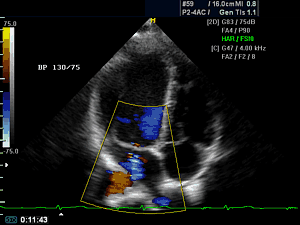

• УЗИ сердца, т.е. эхокардиография, включая допплер и оценку кровотока на новейшем 3D и 4D ультразвуковом цифровом сканере Premium класса, мирового лидера General Electric (США).